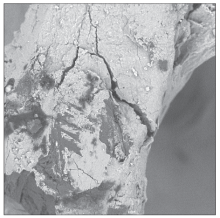

目的 研究小鼠胚胎成骨细胞MC3T3-E1在低温氩氧等离子体处理的无机牛骨上的黏附、增殖及分化特征。方法 使用低温氩氧等离子体对无机牛骨进行表面活化(实验组)后,使用扫描电子显微镜(SEM)观察无机牛骨表面形貌的变化,X射线光电子能谱分析(XPS)检测表面元素的组成。将MC3T3-E1细胞接种于低温氩氧等离子体处理的无机牛骨表面,使用SEM观察细胞的黏附形态,CCK-8法检测细胞1、3、5 d的增殖变化,碱性磷酸酶(ALP)法检测细胞7、14 d的分化状态。以不作处理的无机牛骨作为对照。结果 对照组与实验组的表面形貌无明显改变;在表面材料的元素组成上,实验组表面碳元素减少,氧、钙、磷元素均增高。实验组MC3T3-E1细胞的黏附更充分,细胞伸出伪足;培养1、3、5 d时,实验组细胞增殖数量明显高于对照组;培养14 d时,实验组ALP活性明显高于对照组(P<0.05)。结论 低温氩氧等离子体处理对无机牛骨表面小鼠胚胎成骨细胞的黏附、增殖及分化具有一定的促进作用。